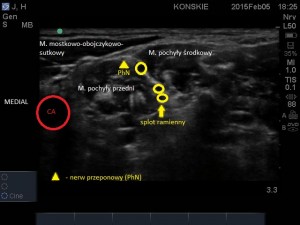

- Nerw przeponowy, splot ramienny

W obrazie ultrasonograficznym możemy także odnaleźć powierzchownie położoną blaszkę przedkręgową powięzi szyi (hiperechogeniczna linijna struktura), którą przykryty jest splot, zarys mięśnia mostkowo-obojczykowo-sutkowego a także głębsze struktury takie jak tętnica kręgowa i wyrostki poprzeczne kręgów szyjnych. W bezpośrednim sąsiedztwie splotu, na przedniej powierzchni mięśnia pochyłego przedniego, tuż pod blaszką przedkręgową położony jest nerw przeponowy. Takie implikacje anatomiczne sprawiają, iż jednostronna blokada nerwu przeponowego jest praktycznie nieunikniona przy wykonywaniu blokady splotu ramiennego z dostępu pomiędzy mięśniami pochyłymi z wykorzystaniem standardowych dawek LMZ (Film poniżej).